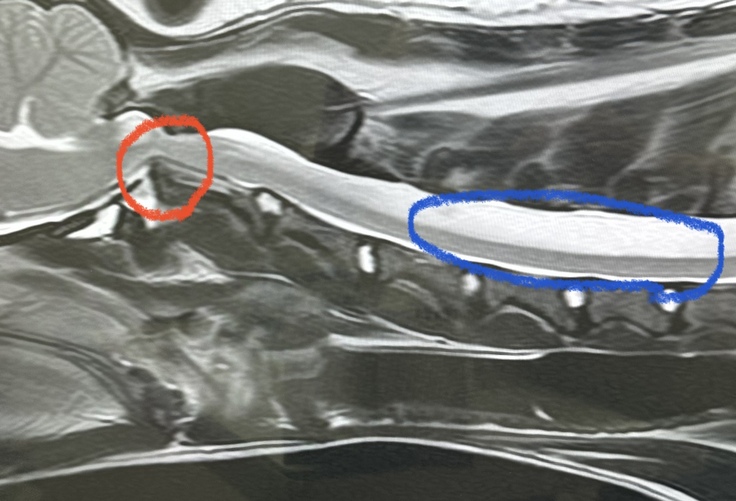

先天的な軸椎歯突起不全による

環軸椎亜脱臼と判明しました。

歯突起の形成不全により骨と骨が

不安定で神経を圧迫することで

痛みを引き起こしている状態です。

本来あるべき場所から骨が上に突き上げて

神経を圧迫して細くなっているのが

MRIでも分かります。(赤丸部分)

あと、MRI検査で分かったのが

たぁ坊の神経の3分の2が

水分が多く白くモヤがかかっていて

これが亜脱臼に起因して引き起こしているのか

これからも経過が必要との事と、

脊髄空洞症という病気に移行する可能性が

あるかもしれないと指摘されました。

(画像青丸部分)